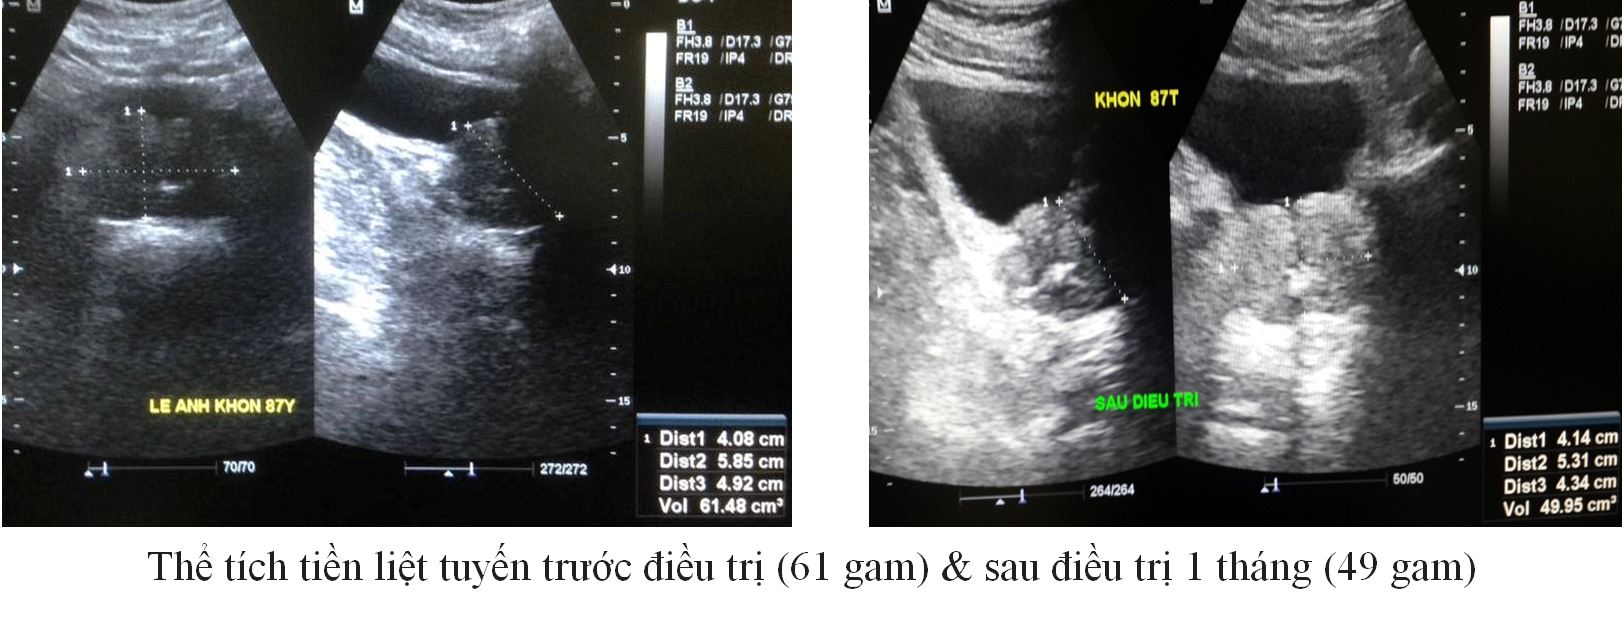

Trường hợp 5:

– BN: Kh, 87 Tuổi

– Tiểu khó, nhiều lần ( 8 lần trong đêm)

– Thể tích TLT : 61 gam

PV (gam) |

61 |

50 |